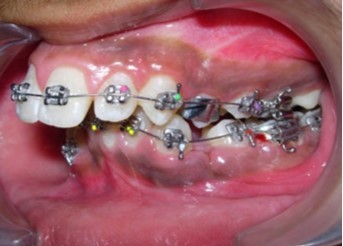

Initial alignment was done with upper and lower 0.014-inch nickel titanium archwires (Figure 6a,Figure 6b,Figure 6c). This was followed with 0.016-inch nickel titanium archwires. Space for blocked out 42 was created by an open coil spring on a 0.018-inch stainless steel archwire. Deep bite was corrected with a lower 0.016-inch reverse curve nickel titanium wire. Extraction spaces in the maxillary and mandibular dental arches were closed with 9mm nickel titanium retraction coil springs attached to crimpable hooks on 0.017 x 0.025-inch stainless steel archwires and finishing and detailing was completed with 0.019 x 0.025-inch stainless steel archwires.

Figure 6b.Initial levelling and alignment – Upper / Lower 0.014-inch nickel titanium wires – Right

Initial levelling and alignment – Upper / Lower 0.014-inch nickel titanium wires – Right

Figure 6c.Initial levelling and alignment – Upper / Lower 0.014-inch nickel titanium wires – Left

Initial levelling and alignment – Upper / Lower 0.014-inch nickel titanium wires – Left